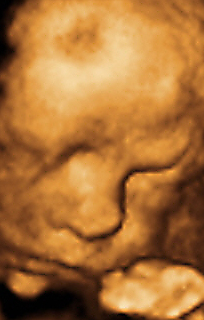

香港结构超声波照片

结构性超声波, 四维 香港, 四维结构性超声波 结构性超声波, 四维 结构性超声波, 四维 香港, 四维结构性超声波 结构性超声波, 四维 香港, 四维结构性超声波 结构性超声波, 四维 结构性超声波, 四维 结构性超声波, 四维 香港, 四维结构性超声波 结构性超声波, 四维 香港, 四维结构性超声波 结构性超声波, 四维 结构性超声波, 四维